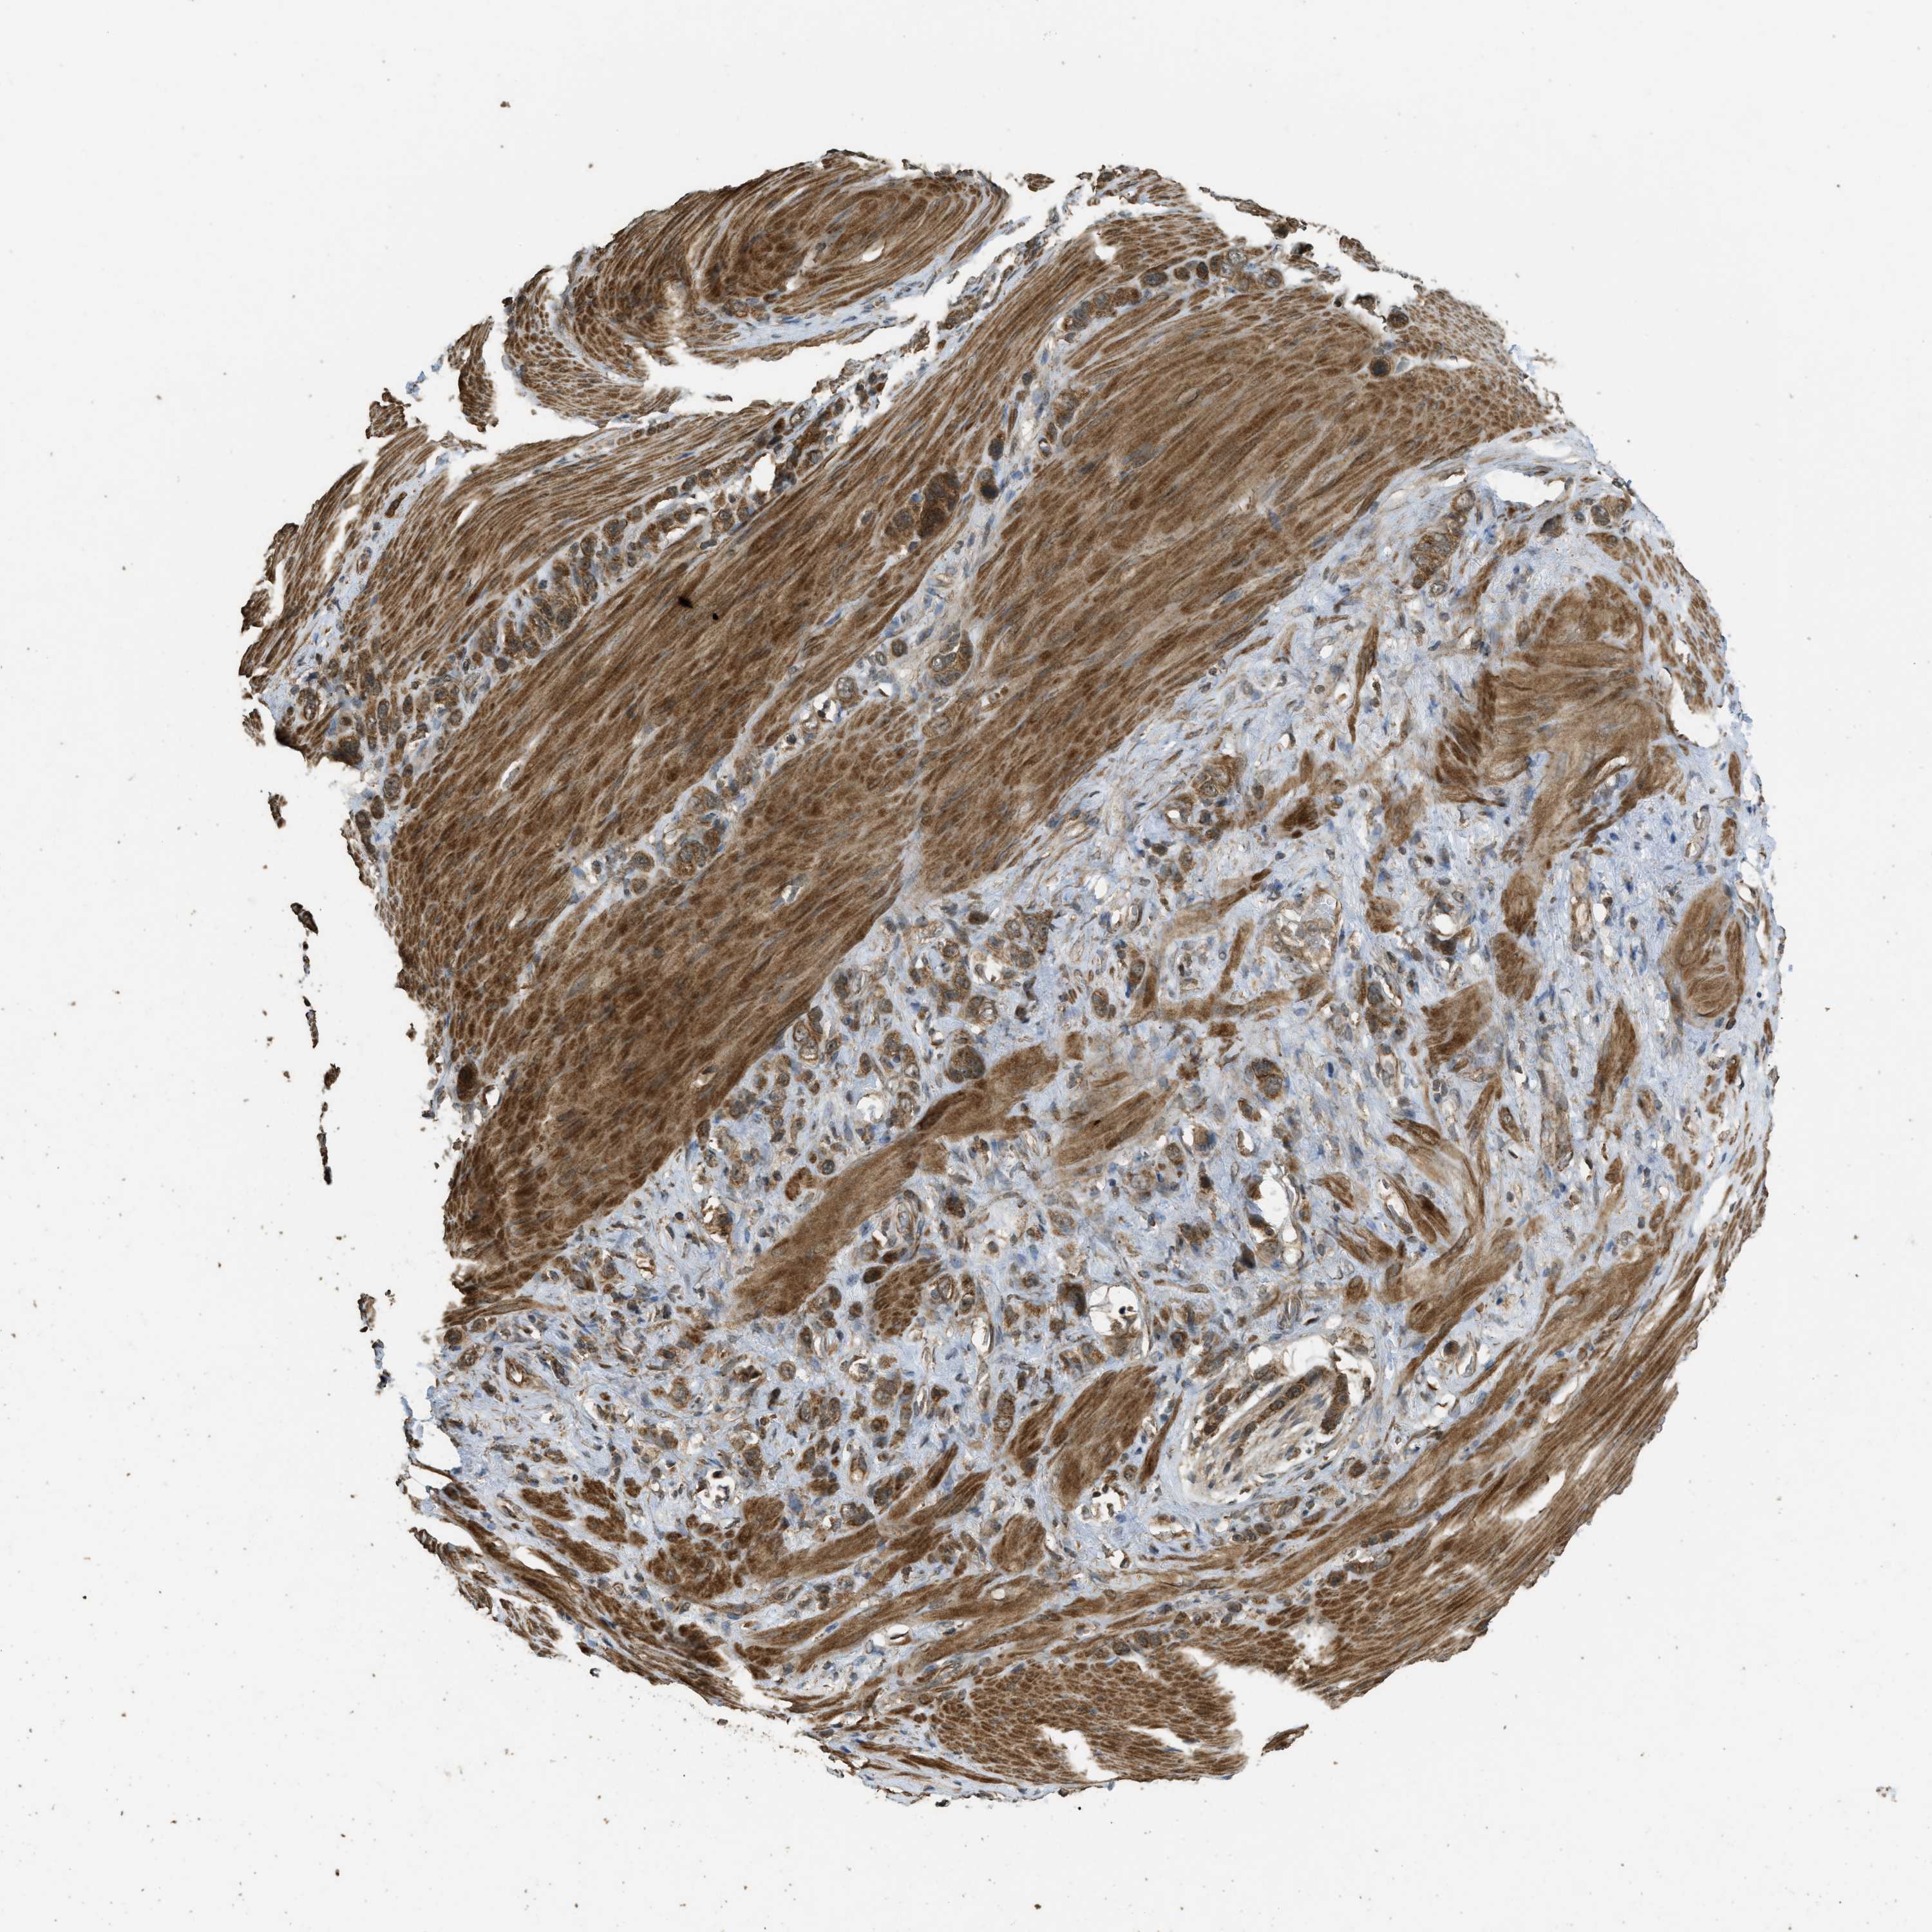

STOMACH CANCER - Protein expressioni

A mouse-over function shows sample information and annotation data. Click on an image to view it in a full screen mode. Samples can be filtered based on level of antibody staining by selecting one or several of the following categories: high, medium, low and not detected. The assay and annotation is described here.

Note that samples used for immunohistochemistry by the Human Protein Atlas do not correspond to samples in the TCGA dataset.

Antibody stainingi

Antibody staining in the annotated cell types in the current human tissue is reported as not detected, low, medium, or high, based on conventional immunohistochemistry profiling in selected tissues. This score is based on the combination of the staining intensity and fraction of stained cells.

Each image is clickable and will lead to virtual microscopy that enables deeper exploration of all samples and also displays staining intensity scores, fraction scores and subcellular localization as well as patient and tissue information for each sample.

Antibody HPA051322

Antibody CAB017111

Staining

High

Medium

Low

Not detected

Intensity

Strong

Moderate

Weak

Negative

Quantity

>75%

75%-25%

<25%

None

Location

Nuclear

Cytoplasmic/membranous

Cytoplasmic/membranous,nuclear

Adenocarcinoma, NOS

Adenocarcinoma, High grade